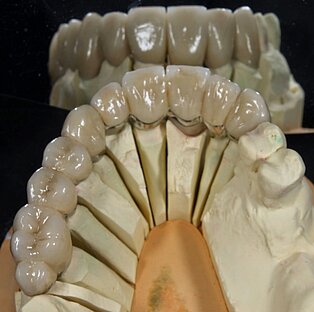

Meisterarbeit von Peter Dengel

Vom Langzeitprovisorium zur TEK 1 Arbeit